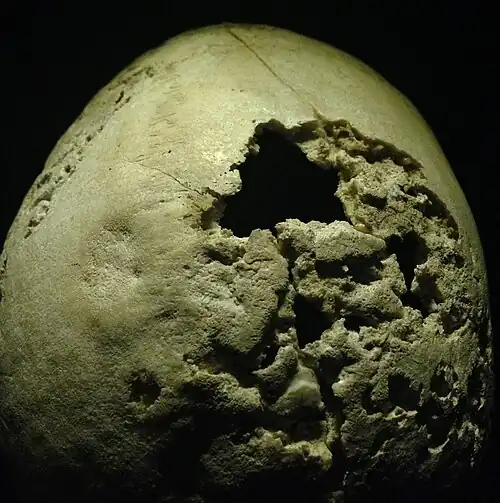

| Section of human skull damaged by late stages of neurosyphilis | |